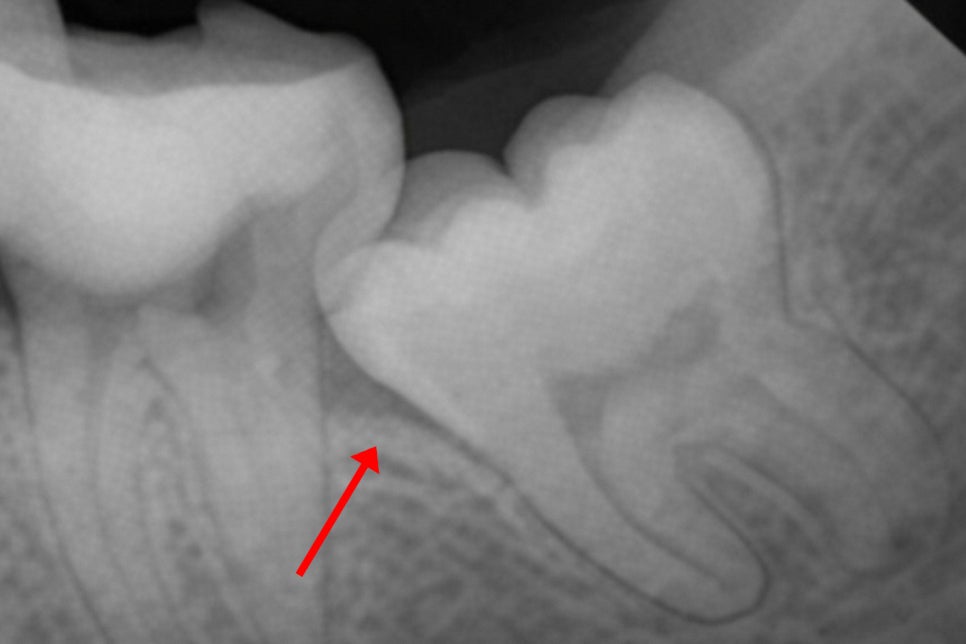

치조골 혹은 앞쪽 어금니의 치근을

지속적으로 압박하면서 생긴 압력과 더불어

치관주위염으로 인해 활성화된 파골세포는

치조골을 녹여버려 엑스레이에서

뼈가 검게 투과되어 보이는

골소실 양상이 나타납니다.

이는 치아를 지탱하는 뼈의 높이가

낮아졌음을 의미합니다.